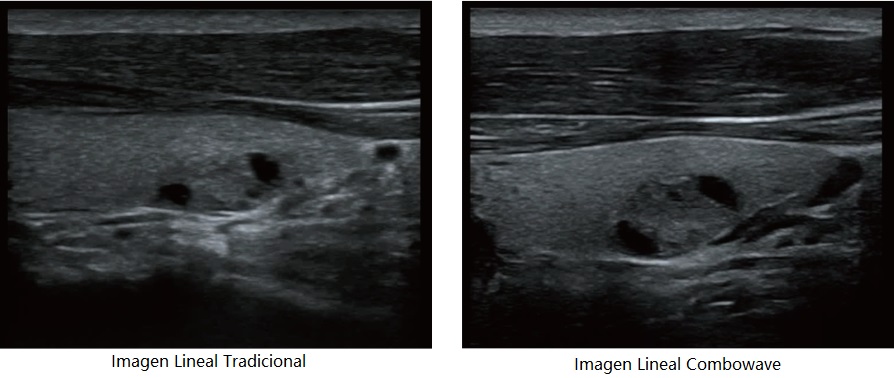

Transductores ComboWave

En comparaciĂłn con los sensores tradicionales, los transductores ComboWave utilizan un nuevo tipo de material piezoelĂ©ctrico compuesto que optimiza notablemente el espectro acĂșstico y reduce la impedancia acĂșstica. AdemĂĄs de integrarse con la tecnologĂa Ășnica 3T de Mindray, los transductores lineales ComboWave ofrecen un rendimiento sobresaliente con una gran resoluciĂłn de imagen y uniformidad en ecografĂas vasculares, de tiroides, de mama, etc.